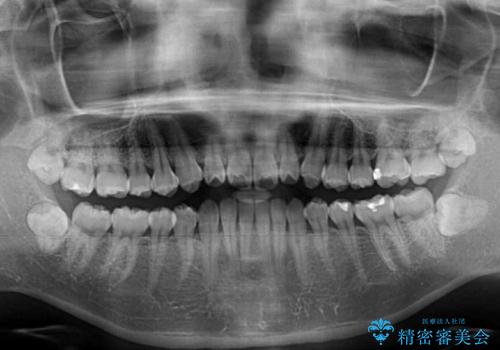

- 下唇に上の前歯が当たることを気にして来院された患者様です。

上顎の親知らずを抜去し、歯列全体を後方に移動させるとともに、IPR(歯と歯の間を削る)を行うことで口元の閉じにくさを改善していくこととしました。

咬合力が強く、マウスピースを介した咬み込みが顕著であったため、奥歯の咬みにくさやIPRのスペースが改善しにくく、治療期間が思った以上にかかってしまいました。